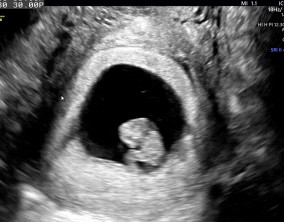

심장소리 이후, 함께 웃게 된 임밍아웃

유정원장님 치료 과정 내내 항상 따뜻하게 진료해 주셔서 감사한 마음이 큽니다. 덕분에 불안한 순간에도 마음을 다잡고 치료를 이어갈 수 있었습니다.